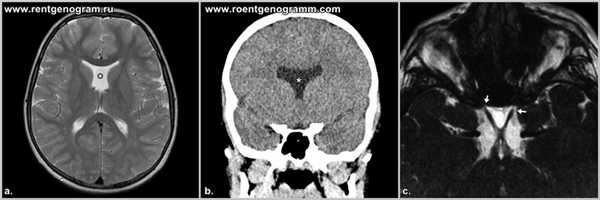

- КТ головного мозга. При компьютерной томографии определяются широко расставленные передние рога, высокое стояние третьего желудочка, параллельный ход медиальных стенок боковых желудочков. КТ производится в рамках постнатальной диагностики.

- МРТ головного мозга. Для максимально точной визуализации степени агенезии или гипоплазии мозолистого тела новорожденным выполняется магнитно-резонансная томография в трех плоскостях. По показаниям МРТ может рекомендоваться беременным женщинам для исключения несовместимых с жизнью сочетанных пороков ЦНС.

Септооптическая дисплазия (синдром de Morsier) является одной из форм лобарной голопрозэнцефалий. Характеризуется отсутствием прозрачной перегородки, гипоплазией зрительных нервов, хиазмы и воронки.

Сочетанная гипоплазия зрительных нервов и отсутствие или гипогенезия прозрачной перегородки, в 2/3 случаев сопровождающаяся гипоталамо-гипофизарной дисфункцией.

Прозрачная перегородка не формируется, таким образом отсутствует разделение боковых желудочков, так же отсутствуют межжелудочковые отверстия, связывающие боковые и третий желудочек и в результате образуется единая вентрикулярная полость. Кроме того имеется двустороннее недоразвитие зрительных нервов, диаметр их уже.